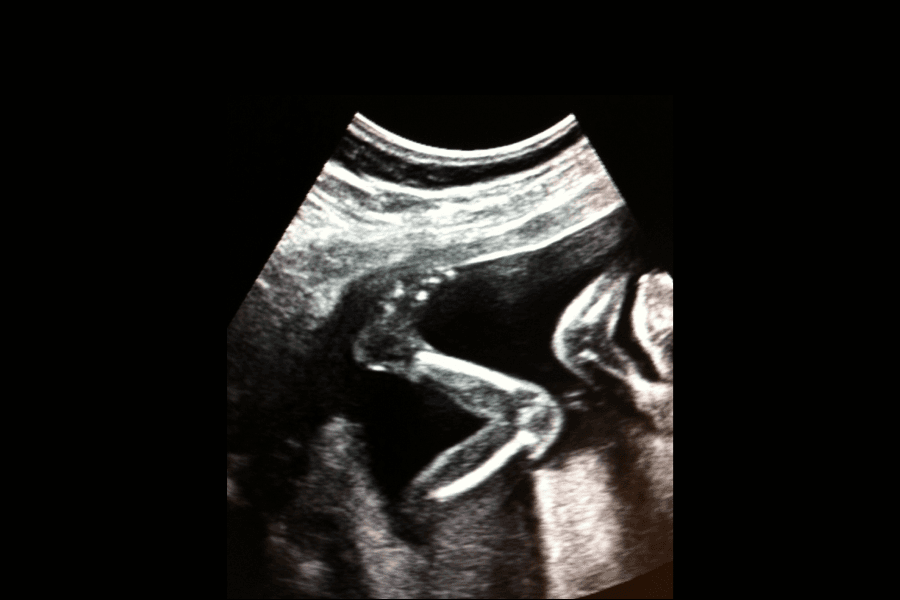

Barnets måde at bevæge sig på i maven varierer fra barn til barn – de kan bevæge sig lidt eller meget og på vidt forskellige tidspunkter. Barnet laver også små bevægelser, som er svære eller umulige at fornemme. Barnet sparker, øver sig i at trække vejret og synke, laver gribebevægelser og træner sin sutteevne. Det gør altså meget mere end at sparke.

Hvordan du som gravid mærker fosterbevægelserne afhænger af barnets personlighed, hvor meget plads barnet har, hvordan barnet ligger i livmoderen og moderkagens placering.